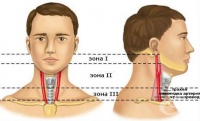

S10.8 Повърхностна травма на други части на шията

S10.9 Повърхностна травма на неуточнена част на шията

S11 Открита рана на шията

Рана, при която има пробив или разкъсване на кожата на шията се нарича открита рана на шията. Повече...

S11.0 Открита рана, обхващаща ларинкса и трахеята

Наранявания на ларинкса и трахеята, в резултат от травми са доста необичайни. Епидемиологичната хара...

S11.1 Открита рана, обхващаща щитовидната жлеза

Проникващи наранявания на врата, включваща щитовидната жлеза са относително редки. Въпреки че травма...

S11.2 Открита рана, обхващаща фаринкса и шийната част на хранопровода

Открита рана, обхващаща фаринкса и шийната част на хранопровода са рядкост. Епидемиологични проучван...

S11.7 Множествени открити рани на шията

Физическо нараняване, при която се получава присъстващо едновременно на няколко части от шията е мно...

S11.8 Открита рана на други части на шията

Рани от порязване, разкъсване, пробождане или ухапване причинени от остри предмети на шията представ...

S11.9 Открита рана на неуточнена част на шията

Открита рана в областта на шията предизвикана от механична сила, травмираш агент представлява открит...